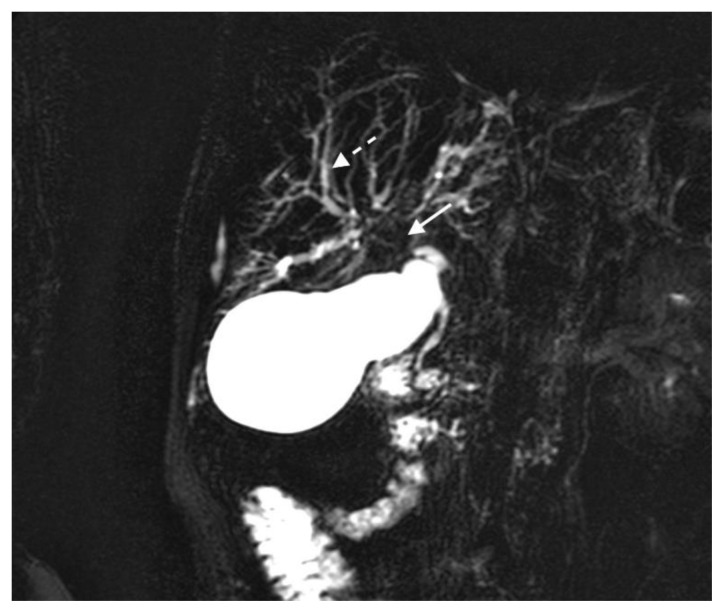

The MRI revealed soft tissue encased the proximal common bile duct (CBD) and biliary hilum, resulting in a 4cm-long stricture, with increased upstream intrahepatic biliary dilatation (Figures 5, 6). The hepatic parenchyma demonstrated diffuse heterogeneous enhancement, without a focal mass or pseudotumor, consistent with inflammatory changes. The pancreas demonstrated parenchymal T2 hyperintensity and T1 hypointensity with diffuse enhancement, including an enhancing peripheral soft tissue rind, again consistent with autoimmune pancreatitis (Figure 7). The kidneys also demonstrated multifocal regions of abnormal enhancement and restricted diffusion (Figure 9, 10). Persistent enhancing soft tissue surrounding the SMA and IMA was again noted (Figure 11, 12).

Figure 5.

78 year-old male with IgG4-related autoimmune disease.

Findings: Magnetic resonance cholangiopancreatography (MRCP) shows absent fluid signal within the proximal common bile duct and biliary hilum (solid arrow) consistent with a long segment stricture and intrahepatic biliary dilatation (dashed arrow).

Technique: Coronal MRCP MIP (1.5T, TR 300, TE 97.5, Slice spacing 367)